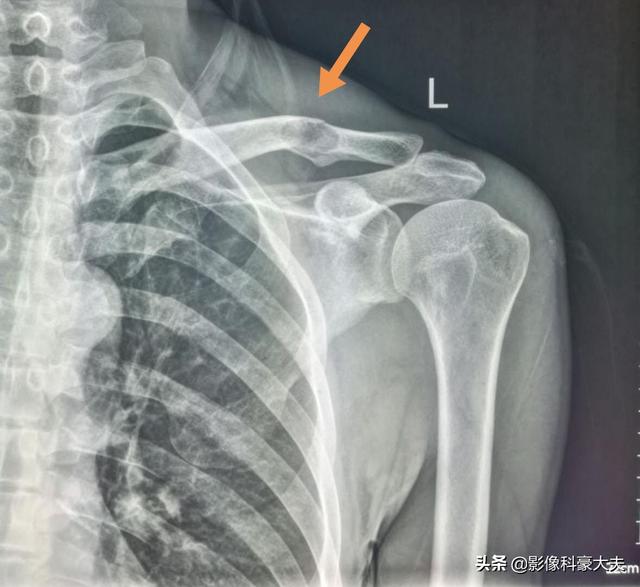

Schlüsselbeinmetastase eines schlecht differenzierten Karzinoms, das seit 5 Jahren mit dem Tumor überlebt hat

Es handelt sich um einen 58-jährigen schwulen Mann, der bei einer leichten Streckung seiner Schulter anhaltende Schmerzen verspürte und bei Röntgenaufnahmen hypodense Herde feststellte:

Es handelte sich um eine pathologische Fraktur, die durch geringe äußere Kräfte auf der Grundlage einer Knochenmetastase verursacht wurde. Es wurde eine Punktion durchgeführt und die Pathologie war eine Knochenmetastase eines schlecht differenzierten Lungenadenokarzinoms.

Dieser unregelmäßige Knoten in der linken Lunge ist der Primärherd, der nur 2,6 cm groß ist. Lungenkrebs mit Knochenmetastasen wie diesem ist nicht mehr operabel. Man kann ihm nicht helfen, Lungenkrebs ist zu häufig und einige der frühen Symptome sind atypisch oder sogar symptomlos.Bei etwa 30 % der Lungenkrebse sind Symptome von Metastasen die erste Manifestation, und Metastasen werden zuerst entdeckt, bevor weiterer Lungenkrebs entdeckt wird.

Glücklicherweise sprach dieser Patient auf die Behandlung an und wird seit fünf Jahren mit einer Kombination aus Chemotherapie und gezielten Therapien behandelt.

Dies ist die Operation zur internen Fixierung eines Schlüsselbeinbruchs, eines pathologischen Bruchs, der ohne chirurgischen Eingriff nur sehr schwer von selbst heilt.

Seine letzte CT-Untersuchung zeigte, dass das primäre Foto stark geschrumpft war, und er hatte Glück, dass er über 5 Jahre lang mit Retention überlebte!